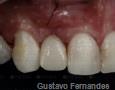

Immediate Implant Placement

Summary Case - By Gustavo Fernandes

4 Months

6 Months

1 Year